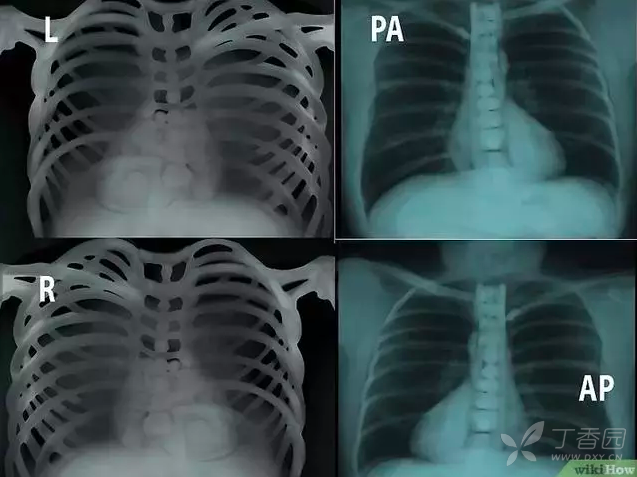

再复习一遍.pa:正位,ap:前后位,l:左侧,r:右侧.

一个小男孩的胸部x光片,pa正位.